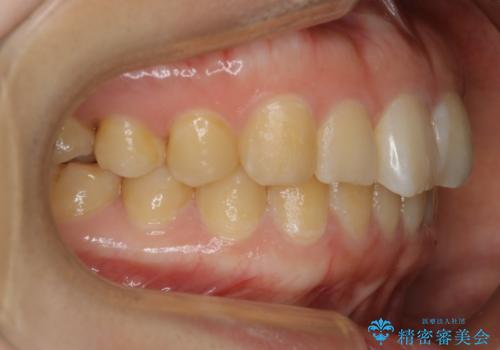

【非抜歯】ガタつきと歯軸を正して長持ちする歯へ

- 歯のガタつきと噛み合わせの改善を主訴に来院されました。

非抜歯で、少量の奥歯の移動と歯列の拡大・IPRを駆使して主訴を改善するための治療計画を立案しました。